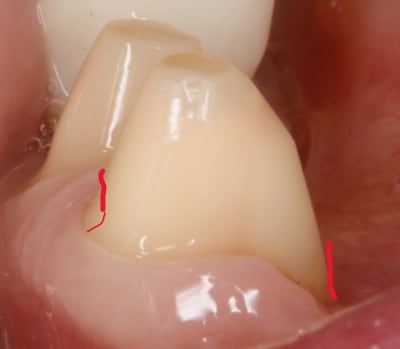

arrive maintenant le congé .

on a vu qu en vest , du fait que ce soit penché à cause des dents du haut , ce serait bien de rajouter une opposition avec la face linguale .

donc au pied si on pouvait rentrer un peu tout en redressant ce serait pas mal .

ben voilà , il sert à ca le congé , le voilà . à faire la férule de PP :-)

en plus ca fait plaisir au labo qui va pouvoir s amuser dessus à faire l artiste .

le congé doit donc servir à réduire la conicité .

c est pour ca qu il doit être fait APRES la face linguale .

puisque que peuchère , la face linguale étant limitée , on s adapte à elle et on parallélise à mort , enfin on essaye .

traits rouges sur photos .